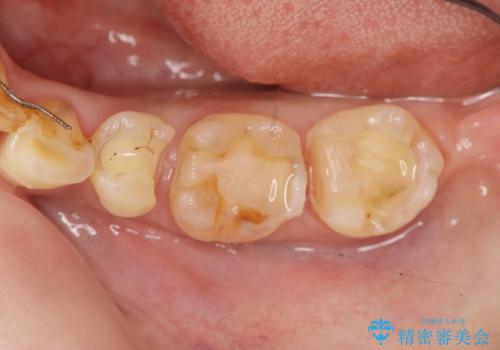

- 他院で銀歯の下部に再発した虫歯の存在を指摘され、精密な治療を求めて来院されました。

銀歯下に虫歯が再発すると神経に近くなり、根管治療を必要とする可能性が高まってしまいます。

健全な歯を削らないように拡大鏡下で丁寧に虫歯を除去することで神経を温存し精密なセラミック治療を行うことができました。

- 15.4万円(セラミックインレー×2)費用は治療当時の料金となります